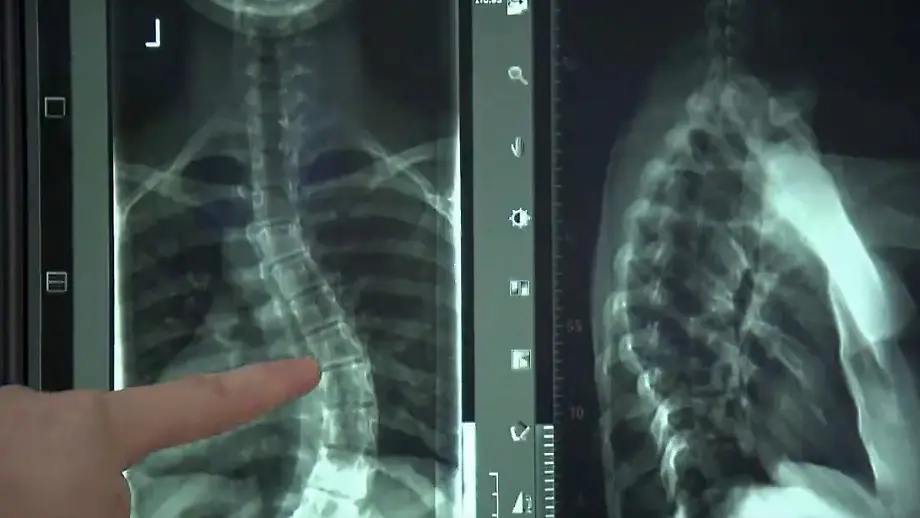

Wann Untersuchung nötig istRückenschmerzen oder Skoliose? Arzt nennt vier Kriterien

03.10.2025, 14:00 UhrLaila Maria Ferchichi, Tochter von Bushido, ist Skoliose-Patientin. "Ihr seid nicht alleine" sagt sie in einem Online-Video. Die Verformung der Wirbelsäule ist verbreitet. Orthopäde Dr. Manke zeigt die vier Kriterien, die auf Skoliose hindeuten, und welche Übungen Schmerzen lindern können.